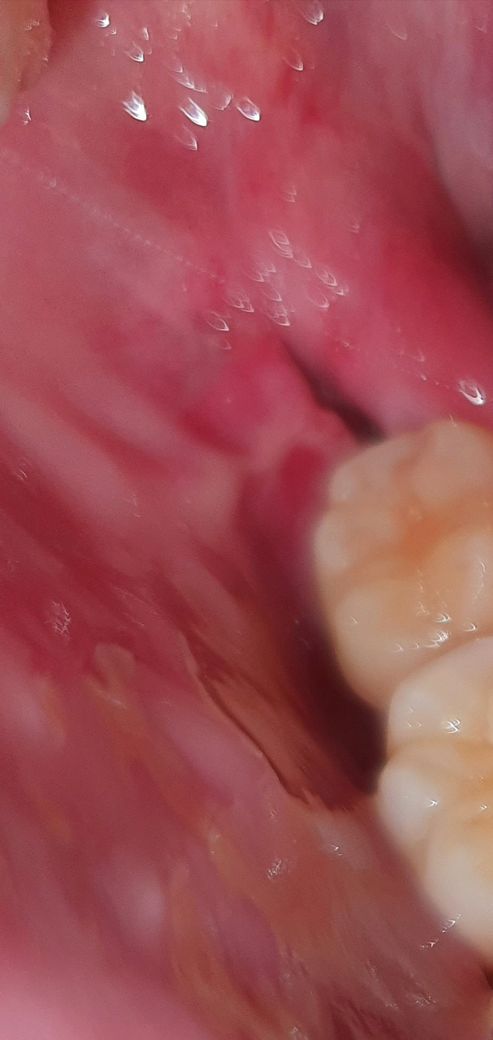

사랑니 뺀뒤 잇몸에 대한 질문입니다(사진 포함)

1.원래 붙어있던 볼쪽 잇몸이 치아와 떨어진것 같습니다.

2.또한 안쪽에 검정색으로 딱지로 추정되는 것이 매우 낮게 존재하고있어 구멍난 부위까지 잇몸이 차오를지 의문입니다.

정상적으로 잇몸이 모두 차오르고 회복될것처럼 보이지가않습니다. 상처라는것이 딱지가 존재하는 곳까지만 회복되는것 아닌가요? 선생님들의 의견이 필요합니다

정상적인 회복과정입니다. 즉 볼쪽 잇몸이 치아와 떨어진 것이 아닙니다. 혈병이 이뤄진 다음에 섬유화를 거치고 나중에 뼈와 잇몸으로 바뀔 것으로 보입니다. 상피가 어느정도 덮히는데도 최소 2주~ 한달 이상 걸리기 때문에 해당 공간이 있는 것은 당연합니다. 통증이나 불편감이 없다면 자연스럽게 주변 잇몸과 조화를 이룰 것으로 보입니다.

사진상으로 사랑니를 뺀지 얼마 되진 않은것같습니다. 6개월이상 되진 않은것같고, 길다면 1-2달정도 된것같습니다.

원래 발치후 처음에는 공간이 보일 수 있습니다. 하지만 시간이 더 지나면 잇몸이 차올라오기 때문에 너무 걱정하실 필요는 없습니다. 감사합니다.